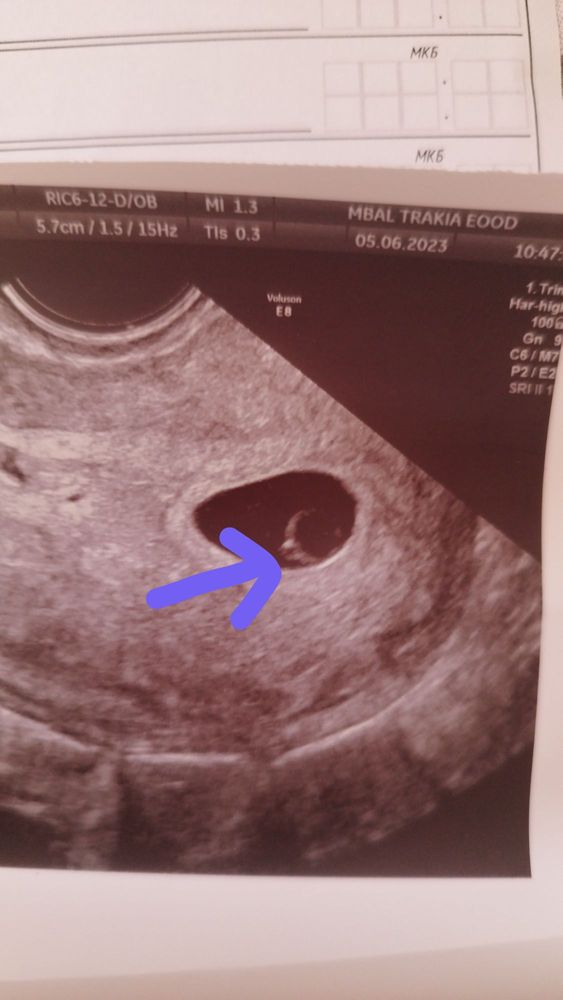

Лилия, здравствуйте поздравляю, не выдержала тоже побежала на узи, тоже радостные новости нашли мою молявочку 7 мм эмбрион и сердечко бъется

07.06.2023

Карина Москвичева, очень рада за вас! А пя сколько? сердечко слышали? Мне вот не дали, может и не должны были, интересно😄

Лилия, пя 34 мм, частота сердцебиение 145, жм 4,4 мм, сердечко сразу включили

Лилия, Изображение